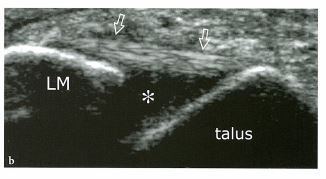

▶좌측: 정상 ATFL 인대 ▶우측: 부분파열된 ATFL 인대 (※출처:근골격계 초음파. Stefano bianchii, Carlo Martinoli)

좌측 그림에서 화살표로 표시되어있는 부분이 정상적인 전거비인대입니다. 뼈와 뼈 사이를 수평하게 잇고, 섬유의 texture와 에코도가 일정하죠. 그와 비교하여 우측 그림을 보시면 중간의 인대섬유가 끊어지고, 부어있는 모습이 보입니다. 에코도 어두워지고 지저분해져있죠. 상처가 난 부위입니다.